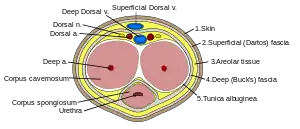

Penile fracture is rupture of one or both of the tunica albuginea, the fibrous coverings that envelop the penis's corpora cavernosa. It is caused by rapid blunt force to an erect penis, usually during vaginal intercourse, or aggressive masturbation.[4] It sometimes also involves partial or complete rupture of the urethra or injury to the dorsal nerves, veins and arteries.[5]

Penile trauma can result from a blunt or penetrating injury, the latter being rarely investigated by imaging methods, almost always requiring immediate surgical exploration. In the erect penis, trauma results from stretching and narrowing of the tunica albuginea, which can undergo segmental rupture of one or both of the corpora cavernosa, constituting a penile fracture.[2]

In the ultrasound examination, a lesion of the tunica albuginea presents as an interruption in (loss of continuity of) the echoic line representing it (Figure 4). Small, moderate, or broad hematomas demonstrate the extent of that discontinuity. Intracavernous hematomas, sometimes without the presence of a tunica albuginea fracture, can be observed when there is a lesion of the smooth muscle of the trabeculae surrounding the sinusoid spaces or the subtunical venular plexus.[2]